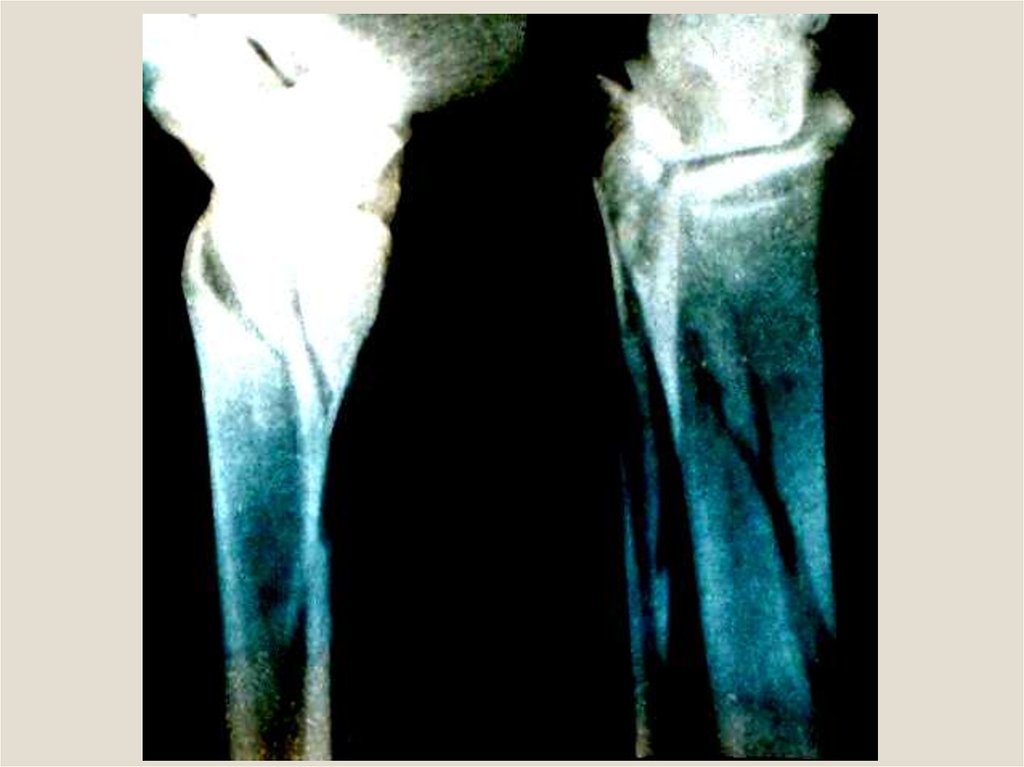

Для внутрикостной (интрамедуллярной)

фиксации используют стержни

Богданова, ЦИТО, Кюнчера и др.

Фиксатор должен плотно входить в

костномозговой канал, перекрывать

линию излома и не менее чем на 8 см

проникать в дистальный отломок.